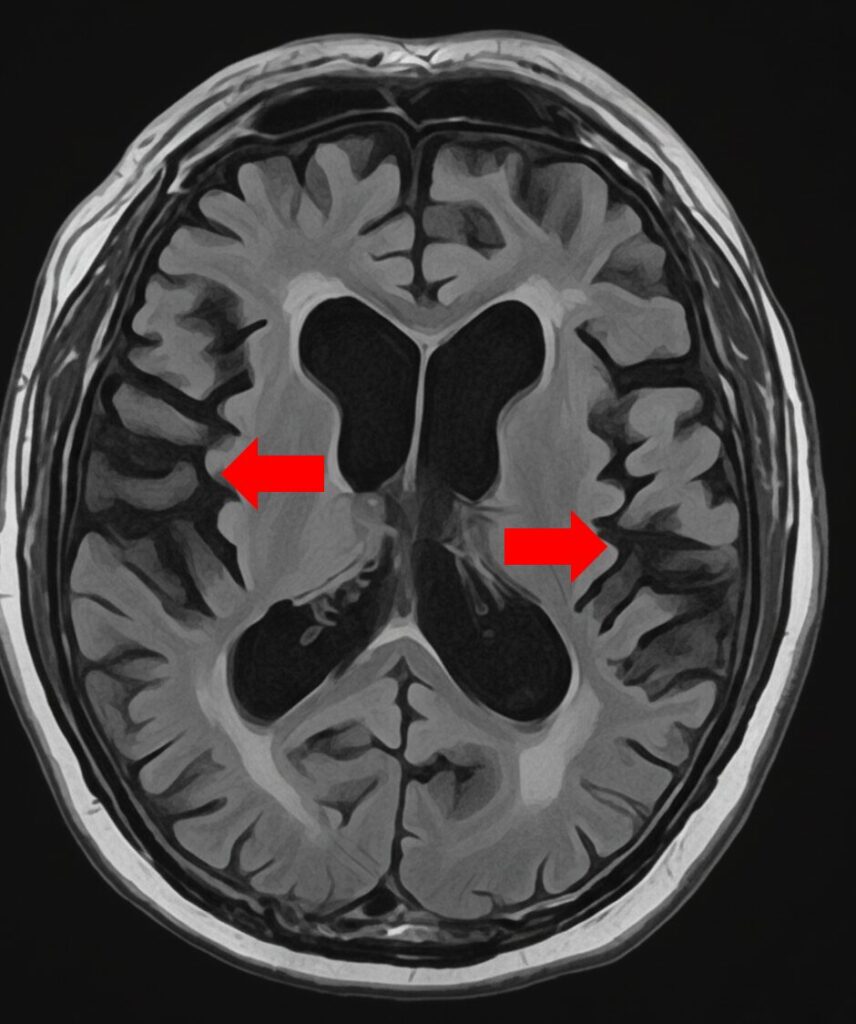

脳萎縮のMRI診断:専門医による評価の視点と検査

MRI検査は、脳の萎縮状態を客観的に確認するために不可欠です。専門医は以下の点を複合的に観察し、萎縮のタイプと原因を推測します。当院では当日MRI検査が可能です。

萎縮の場所とパターンから病態を特定する視点

- 萎縮の場所とパターンから病態を特定する視点

- 海馬周辺の萎縮: アルツハイマー型認知症の初期に強く現れる萎縮パターン。

- 脳全体・脳室の拡大: 加齢やアルコール多飲、または血管性障害による広範囲な萎縮。脳室の拡大も確認される。

- 脳溝の広がり: 脳の溝(脳溝)が深く広がっているかを確認。

血管の病気(微小梗塞)の有無をチェックする理由

微小梗塞・白質病変の所見が多い場合、血管性脳萎縮が強く疑われます。この場合、高血圧や糖尿病などの生活習慣病の管理が非常に重要になります。

海馬に萎縮はみられない

海馬に萎縮が見られる

脳溝は深く広がっている